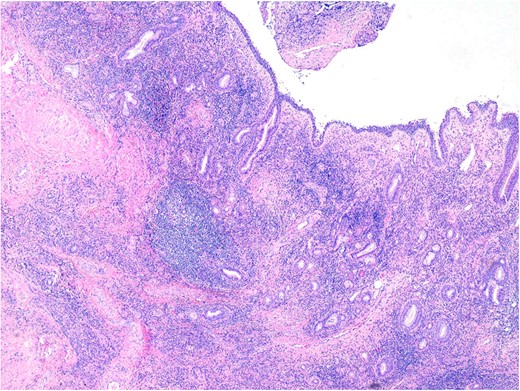

Histopathology demonstrated stromal storiform and perivascular concentric fibrosis with a prominent chronic inflammatory infiltrate (Fig. 2). This consisted of mature lymphocytes, mature plasma cells and eosinophils (Fig. 3). Arteritis (a feature of GPA) was not seen. On digital microscopy, the IgG4 plasma cell counts were 98–120/HPF and IgG4:IgG ratios of 0.4–0.7.

The inflammatory infiltrate is composed of mature lymphocytes, plasma cells and eosinophils. 200× magnification. H&E.